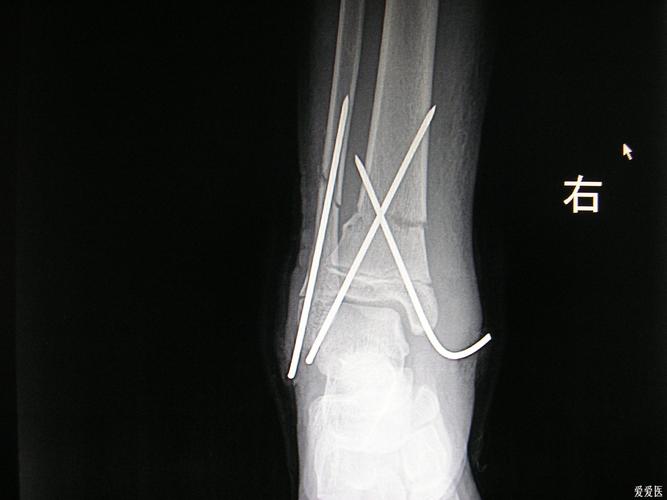

胫腓骨远端骨折闭合克氏针一例